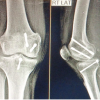

A 34-year-old male was admitted to the emergency department at S N Medical College, Agra, as a case of comminuted fracture proximal tibia and fibula (R) with ipsilateral avulsion fracture of PCL (Fig. 1-4), due to motorcycle-motorcycle collision 3 days before the admission.